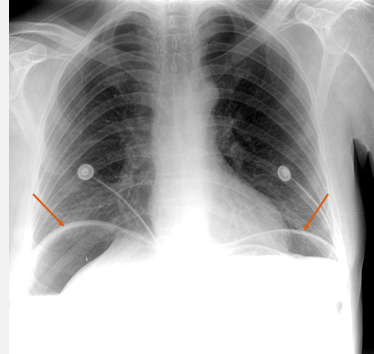

What does this CXR indicate? - Pneumoperitoneum - Pneumothorax - Pulmonary oedema - Consolidation - Pleural effusion

What does this CXR indicate? - Pneumoperitoneum - Pneumothorax - Pulmonary oedema - Consolidation **Pleural effusion: blunted costophrenic edges**